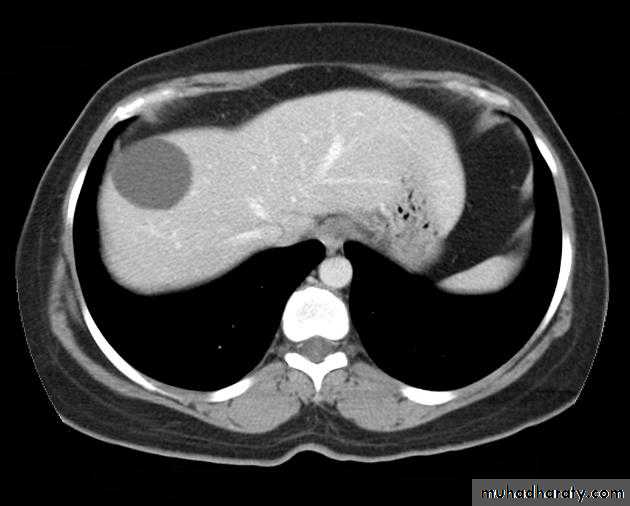

Benign lesions

Hemangioma